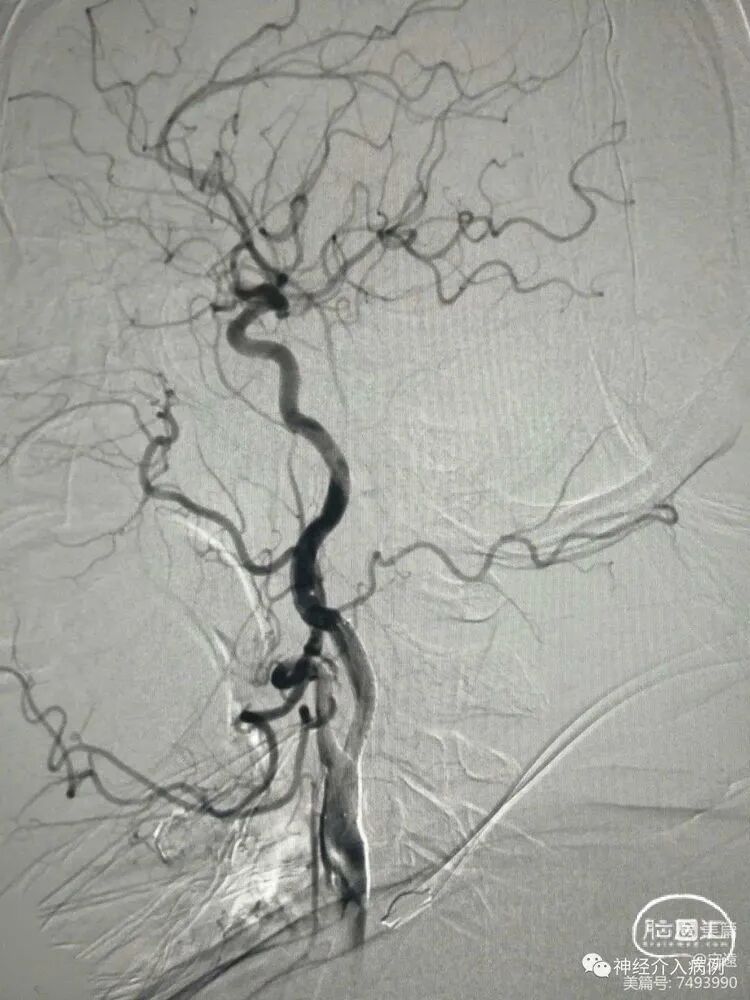

左侧颈内动脉起始部狭窄,血管走形迂曲。

术中保护伞下,(4×30mm)球囊预扩张,扩张时球囊充压8大气压,从心率75次迅速下降至45次,立即推注阿托品1mg,心率逐渐提升至65次分。

预扩张后置入锥形自膨式支架(8×30mm)。

术后血压降低为85/50mmHg。给予小剂量多巴胺3~5ug/Kg分,血压维持在120/60mmHg。